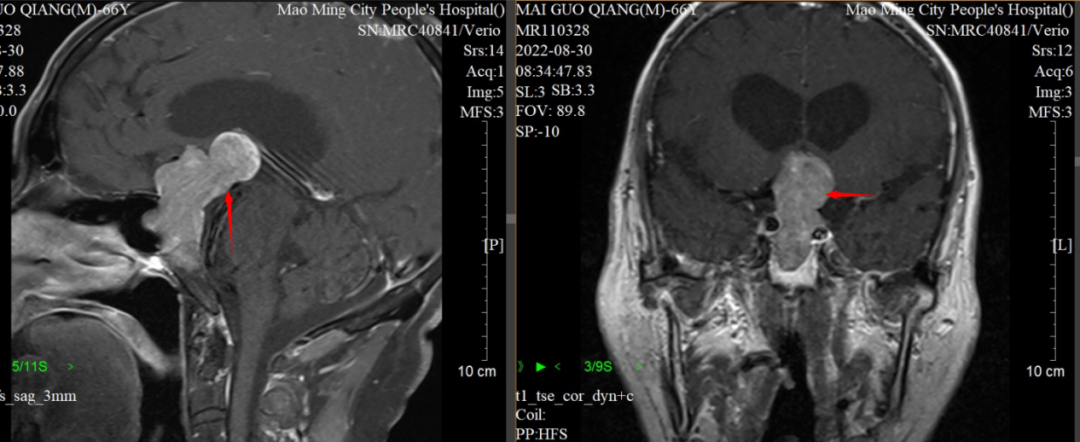

检查结果着实让医院神经外科三区的专家都感到吃惊,原来麦先生颅内长了一个肿瘤并且有6CM大了,已经压迫视神经以及脑干这些重要的神经结构,并引起严重脑积水的症状。

神经外科三区主任周向阳博士指出,麦先生颅内的肿瘤叫垂体瘤,是一种常见的肿瘤类型。虽然它属于良性肿瘤,但具有一定侵袭性,可以沿着颅内的天然缝隙到处侵犯生长。该肿瘤位于鞍区,周围环绕着许多重要的神经和血管,并且位置很深。由此见,传统手术对这种复杂情况来说极为棘手。

▲患者术前MRI显示肿瘤(箭头位置)